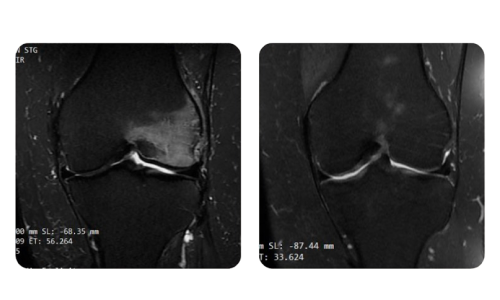

I progressi dei nostri pazienti, misurati prima e dopo la terapia iperbarica, riflettono l'efficacia e l'impatto positivo del trattamento. Scopri i risultati documentati della terapia iperbarica presso la clinica Hyperbarium Oradea, basati su valutazioni cliniche e dati oggettivi che evidenziano miglioramenti significativi in diverse condizioni.